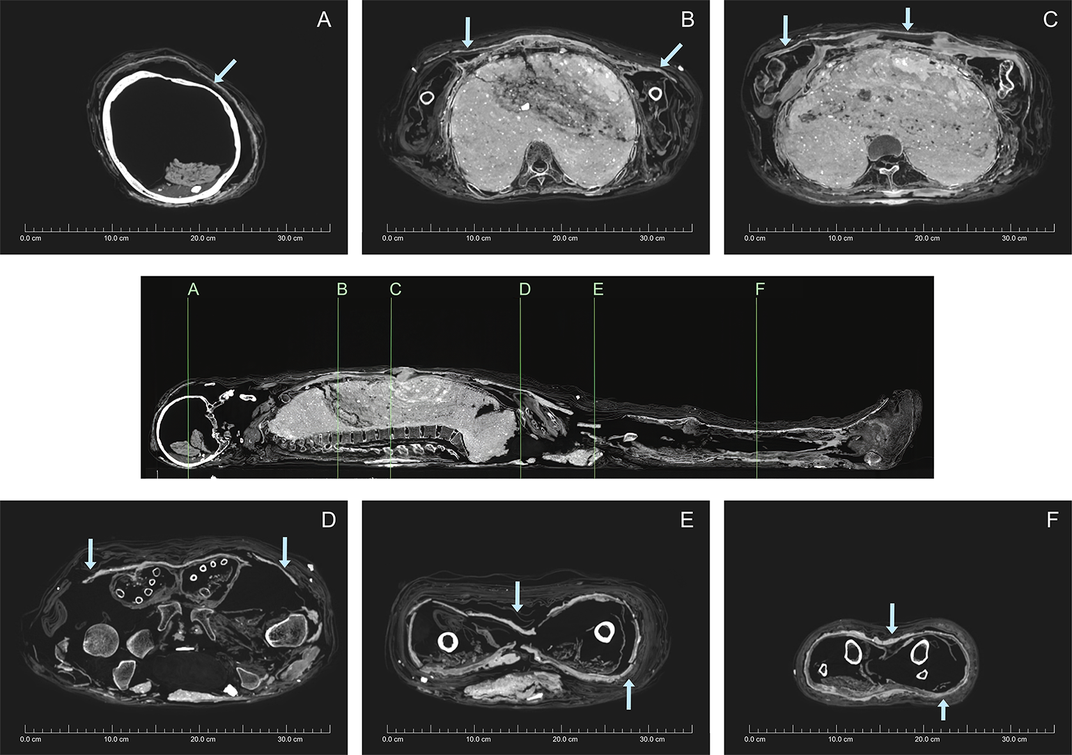

Gần đây, nhà khảo cổ Karin Sowada (Đại học Macquarie, Australia) dẫn đầu một nhóm chuyên gia có phát hiện lớn. Nhóm của ông phát hiện xác ướp được bọc bằng bùn trông như chiếc kén. Đây là điều rất hiếm gặp.

Sau khi qua đời, người phụ nữ được ướp xác và quấn nhiều lớp vải. Thi hài này đầu gối trái và cẳng chân bị phá hủy có thể là do những tên trộm mộ gây ra. Vì vậy, con cháu của người chết đã bọc lại xác ướp và trát bùn xung quanh.

Lần này, những người thợ dùng hỗn hợp phức tạp gồm bùn, cát và rơm giữa các lớp vải quấn bằng lanh. Lớp phủ nền có chất tạo màu từ calcite trắng trong khi lớp trên cùng phủ đất son, một loại khoáng chất màu đỏ.

Khi trát lên xác ướp, lớp bùn vẫn còn ẩm và dễ uốn nặn. Từ đó, xác ướp có hình dáng giống chiếc kén.